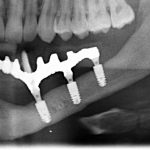

- компьютерная томография, поскольку это единственный способ объективно оценить биотип и измерить линейные параметры участка челюстной кости: